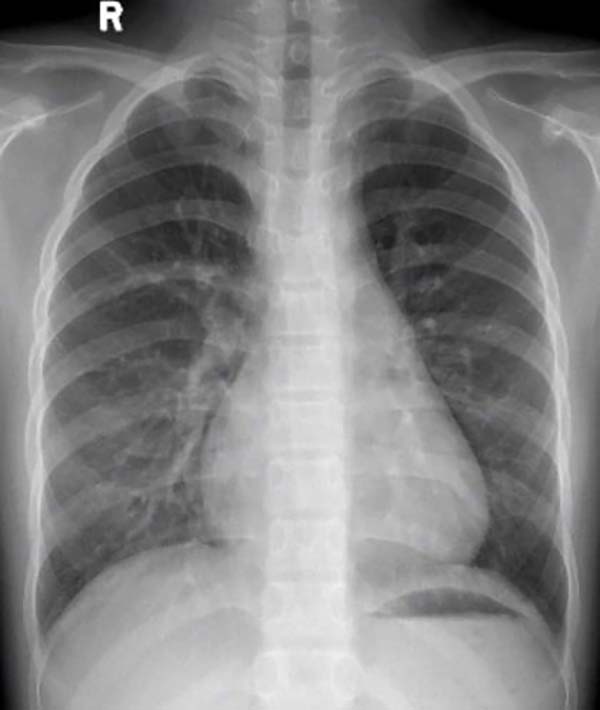

封堵器植入后胸片,无任何异物显影

目前,介入封堵术是先天性心脏病的重要治疗方法。相较于传统金属封堵器永久留存体内可能带来的远期风险,全降解封堵器的最大优势在于其植入后可逐渐被自身组织替代,实现“介入无植入,植入无残留”,从根源上避免了金属异物长期存留的隐患。